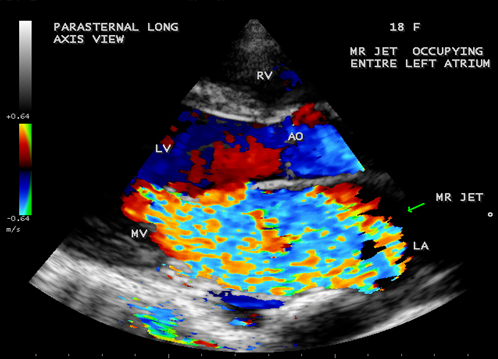

Case 3. Aneurysmal left atrium in a 18 –year old girl due to isolated severe rheumatic mitral regurgitation as shown in Figures 9 to 14. The patient was presented with stroke and treated with anticoagulants and antiplatelet agents and, advised lifelong penicillin prophylaxis and MVR (mitral valve replacement).

Figure 13. Parasternal long axis view showing the severe rheumatic mitral regurgitation jet occupying the entire aneurysmal left atrium in a 18-year old girl.

The extreme dilatation of the left atrium is probably related to the jet of regurgitation (or insufficiency), a finding common to all as shown in Figure 12, the jet occupies the entire left atrium as in Figure 13 and a holosystolic pattern in color M-mode echocardiography as shown in Figure 14.